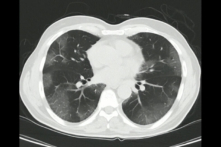

“Phổi trắng” là biểu hiện quan sát thấy trên phim chụp X-quang phổi và CT ngực trong trường hợp viêm phổi nặng. Đối với một người khỏe mạnh, khi chụp X-quang phổi hoặc CT ngực, phổi có màu đen vì bên trong chứa không khí. Khi viêm phổi nặng hoặc có tổn thương phổi cấp tính, các phế nang và mao mạch trong phổi bị tổn thương, máu và dịch tiết vào khoảng kẽ giữa các phế nang và lòng phế nang làm xẹp phế nang. Khi đó trên phim chụp phổi xuất hiện các bóng trắng loang lổ; phổi có màu trắng, do đó được gọi là phổi trắng.